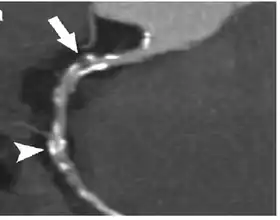

Image of contrast enhanced dual-source coronary CT-angiograph | |